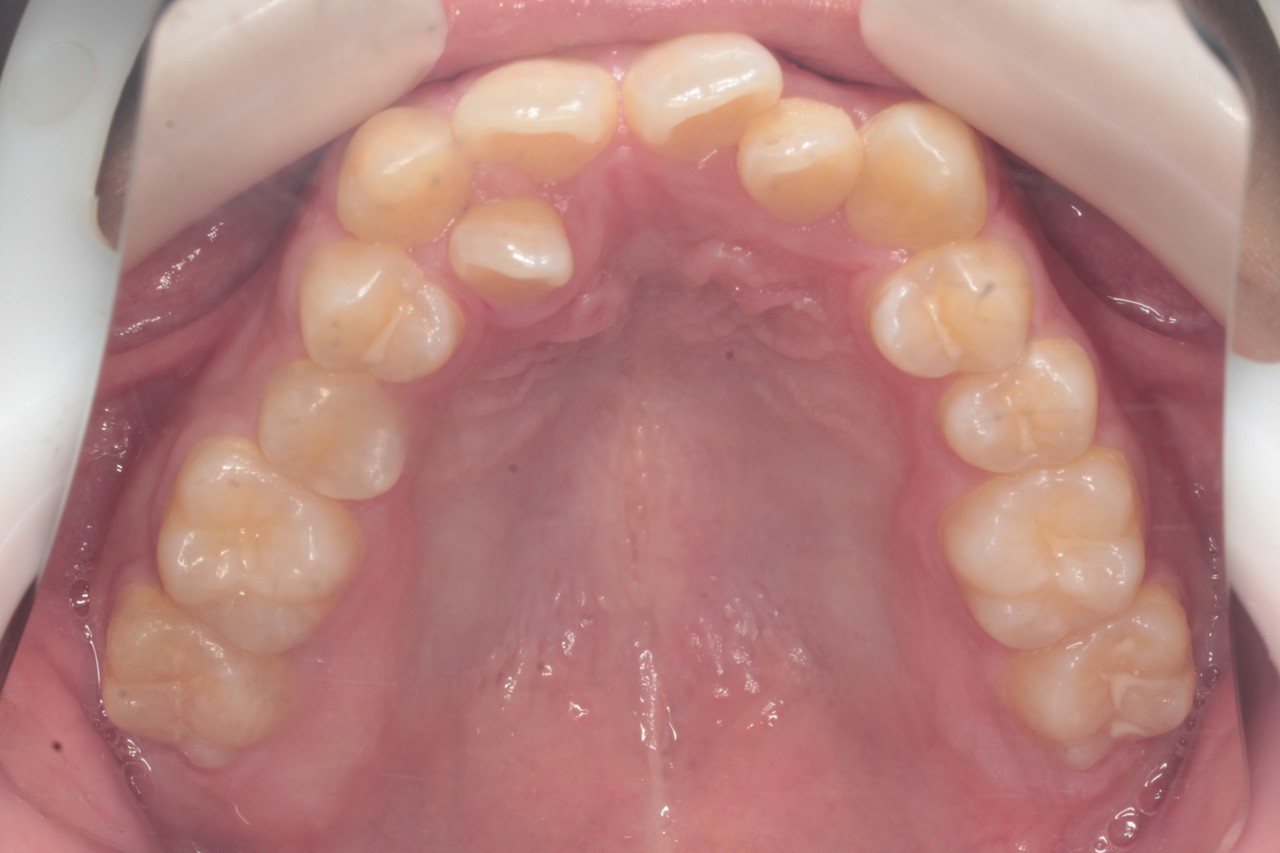

交叉咬合と重度叢生を非抜歯のインビザラインで治療しました

調布市の20代男性

主訴:歯並びをきれいにしたい

使用装置:インビザライン

治療期間:約3年

治療費用:93.5万円(税込)

治療結果:交叉咬合と叢生が改善されました

このレベルの叢生であれば、誰しも抜歯矯正を考えると思います

しかし今回は、抜歯矯正を行うと後のかみ合わせなどのリスクが高く感じたため

親知らずの抜歯にとどめ、奥歯をそのスペースに送ることで

前歯が収まるスペースを得ることを考えました